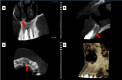

This case report highlights the successful healing of a large periapical lesion through non-surgical root canal retreatment. A 29-year-old male patient presented with a significant radiolucency associated with teeth #21 and #22, initially treated non-surgically. Despite the lesion's size, the treatment, which included thorough canal disinfection and obturation, led to substantial healing. A follow-up cone-beam computed tomography (CBCT) scan after one year confirmed the buccal cortical bone reformation and improvement in the incisive canal area except for the apical region of #21. Subsequently, root canal retreatment was performed for #21. Complete healing was achieved after two years, demonstrating that even extensive periapical lesions can be effectively treated with non-surgical endodontic retreatment, avoiding invasive surgical intervention.